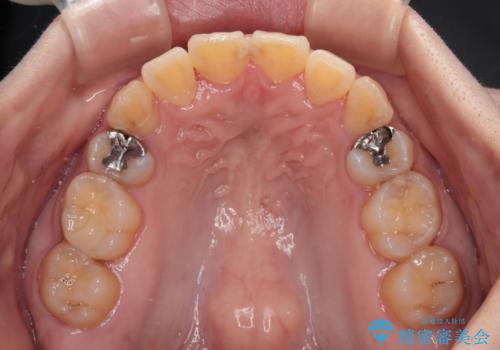

後戻りにリカバリーに少し時間を要しましたが、1年強の期間で無事に治療を終えることができました。